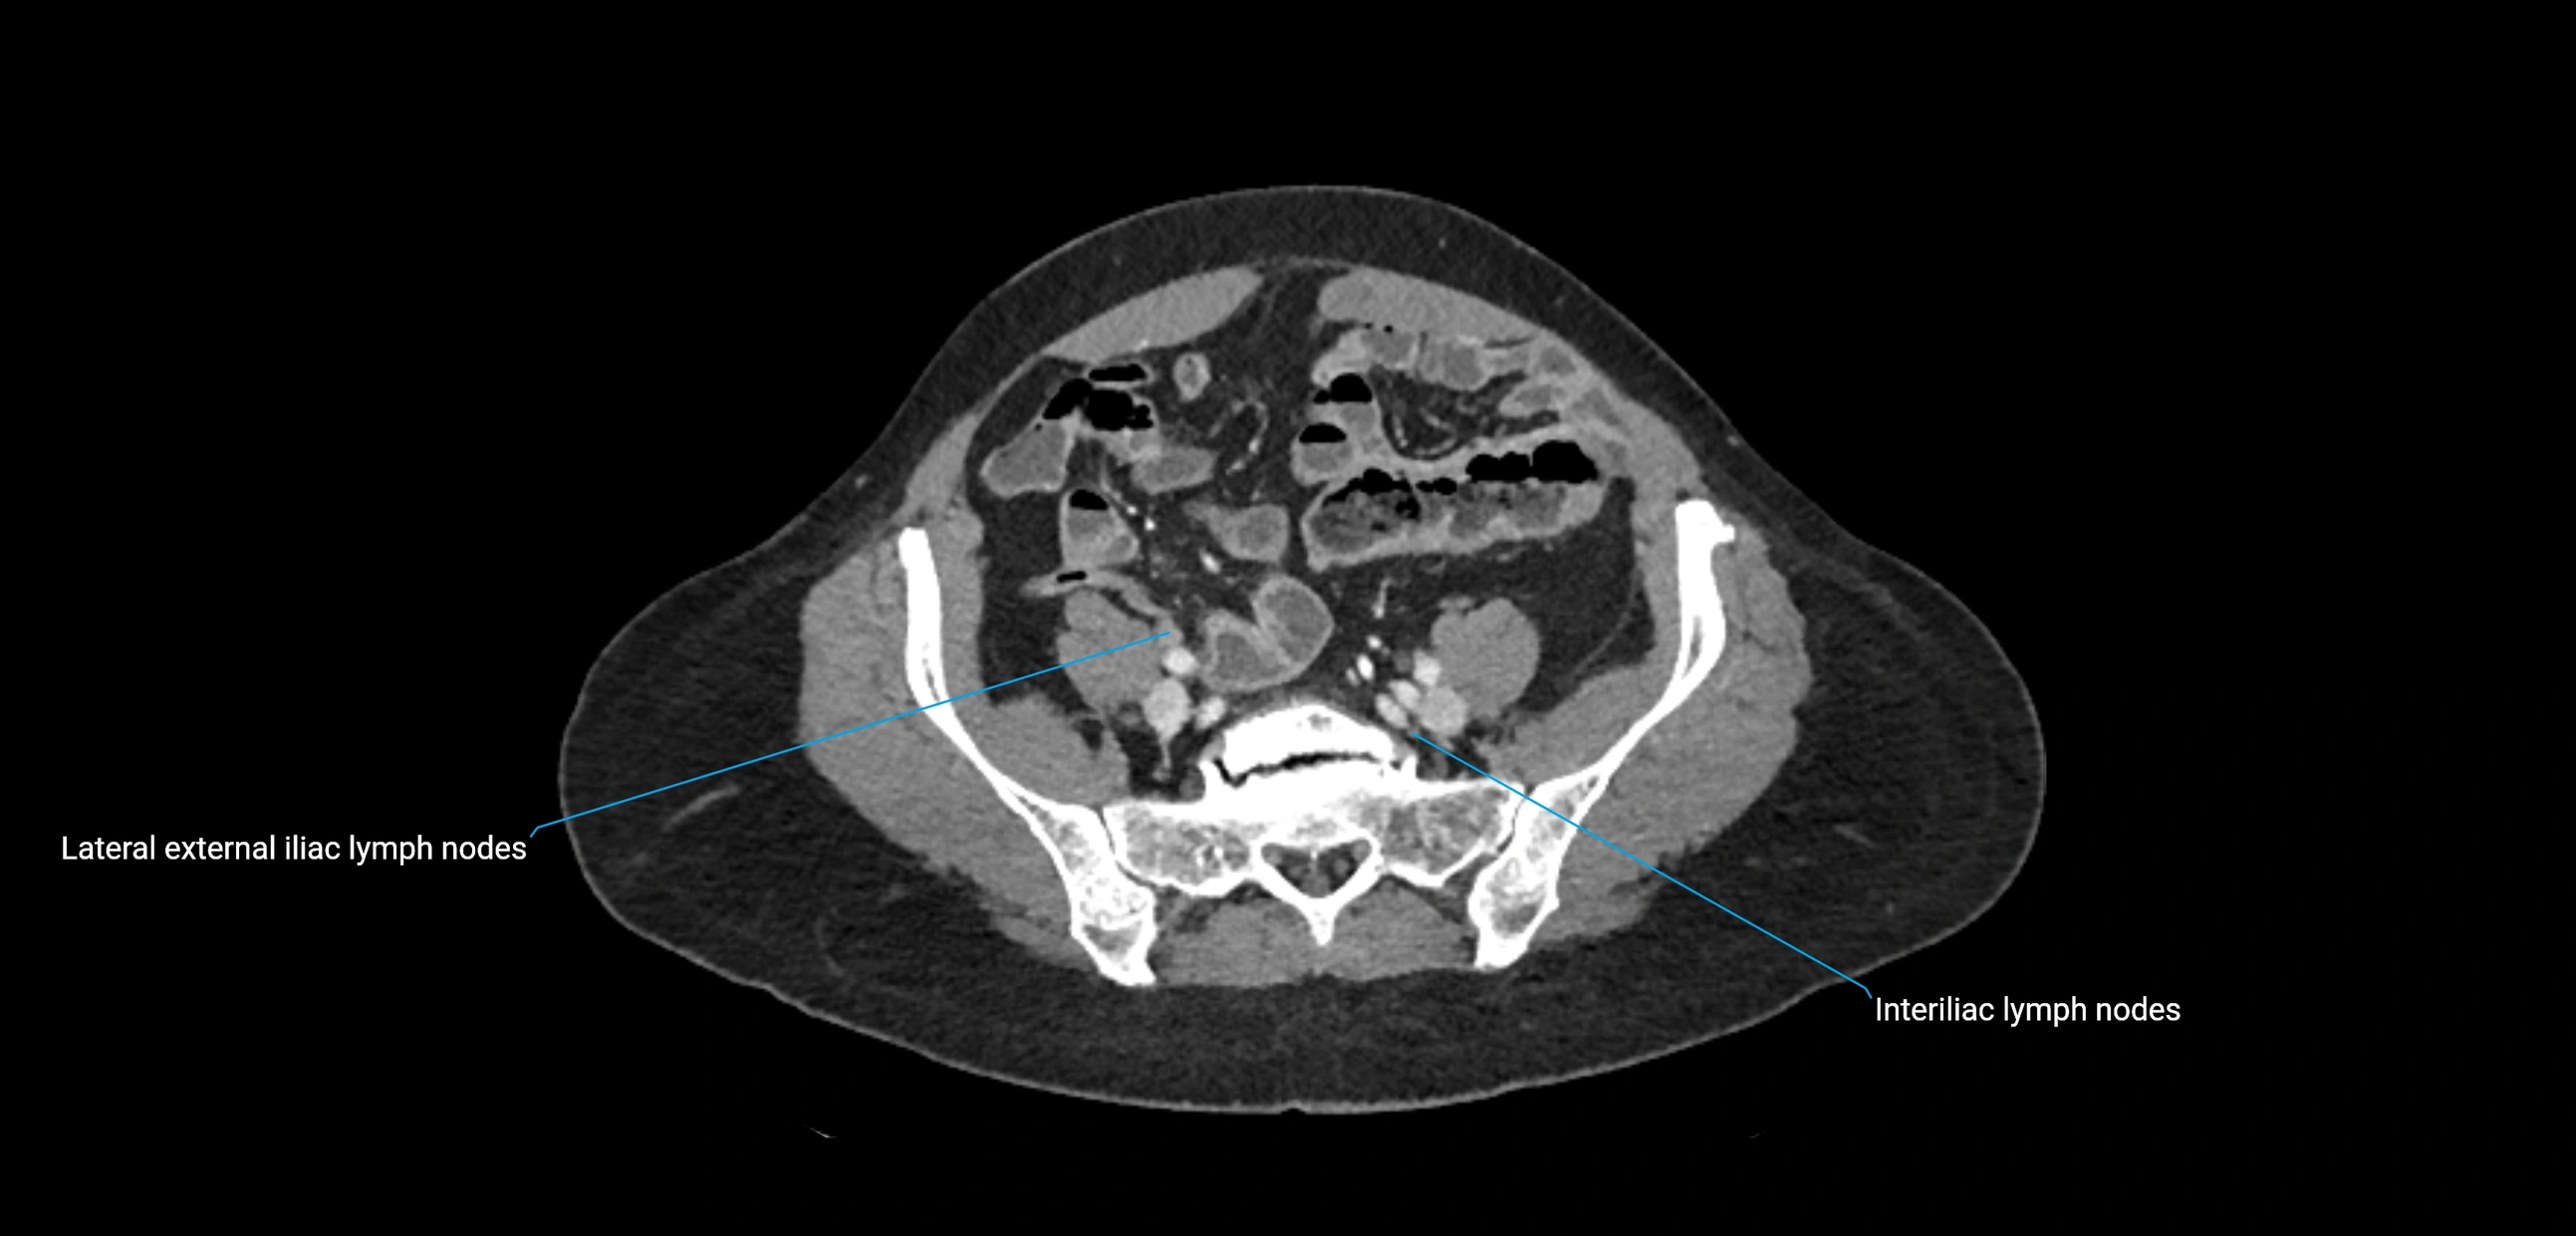

CT image

image